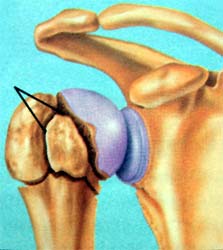

骨性关节炎造成的肩关节软骨破坏,骨刺形成 肱骨头粉碎骨折

全肩关节置换术后示意图 肱骨头置换后X线片